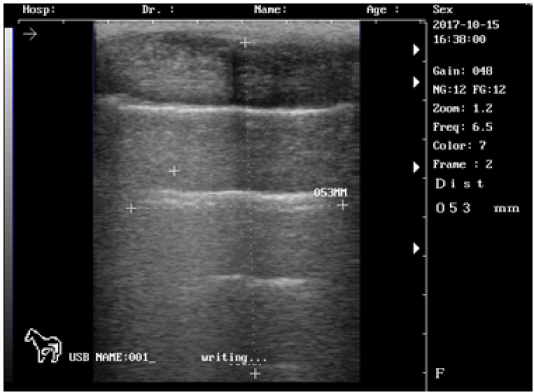

Ultrasound images of the testis of 3 months lamb showing: moderate echogenicity of the testicular parenchyma; mediastinum testicular highly echogenic